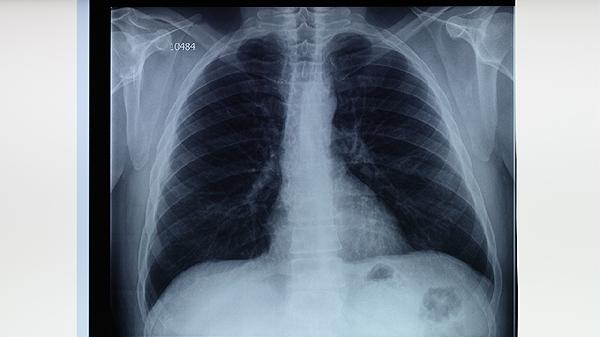

2、影像学检查是评估肺部结节性质的重要手段。低剂量CT扫描可清晰显示结节的大小、形态和密度,帮助医生判断其良恶性。对于直径小于6毫米的结节,通常建议定期随访;直径大于8毫米或形态可疑的结节,需进一步检查如PET-CT或活检以明确诊断。